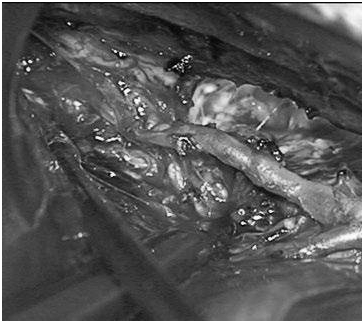

(a)侧位(b)前后位].(c)他取侧卧位,右侧朝下,鼻朝下,中线取水平位以便靠重力牵拉右侧枕叶。窦汇开颅,显露SSS、TrvS、枕较、后纵裂和镰幕交界处。SplenA沿胼胝体压部上升,顺着它可达AVM(续)。